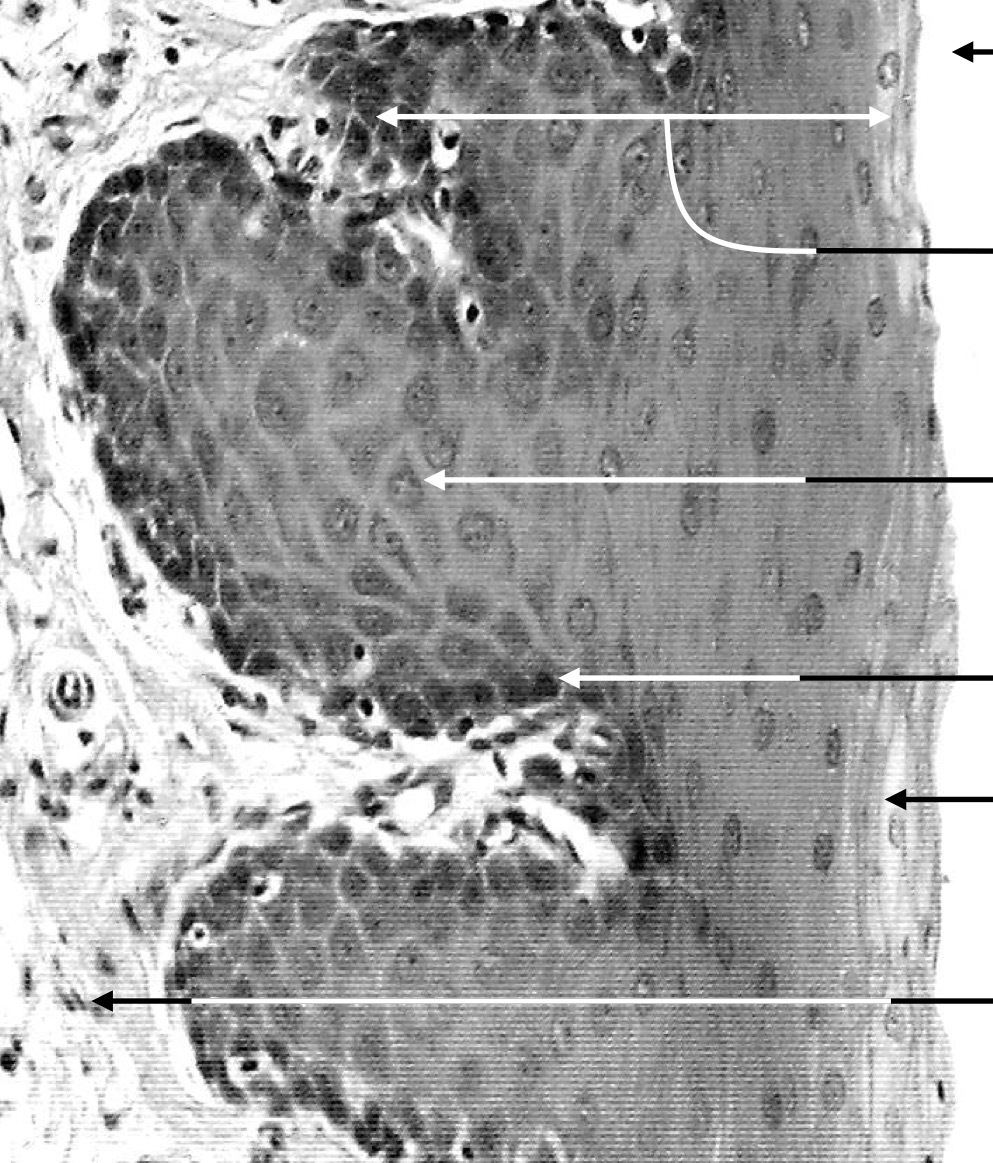

Explain the position of the basement membrane

It is a thin, flexible, acellular layer which lies between epithelial cells and the surrounding connective tissue

Explain the structure of the basement membrane

It is contributed to by the epithelial cells and the subtending connective tissue. Epithelial cells lay down the basal lamina. It’s thickness can be augmented by a variably thick layer of reticular fibrils (type III collagen), form the CT.

Explain the function of the basement membrane

It acts as a strong, flexible layer to which epithelial cells adhere. It also acts as a cellular and molecular filter. NB: the degree to which malignant cells penetrate the basement membrane is highly relevant to prognosis. NB2: the terms basement membrane and basal lamina are used inconsistently in literature